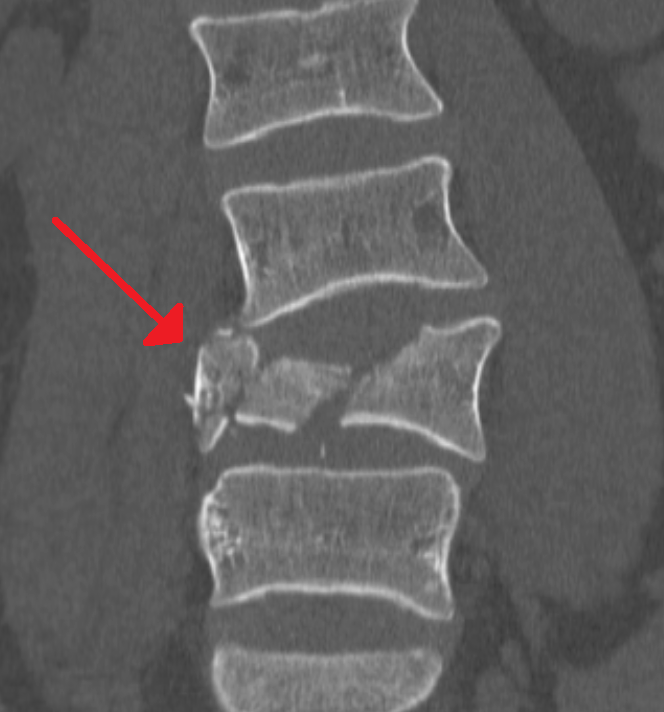

- 척추(허리) 압박 골절

허리뼈가 주저앉는 형태로 부러지는 경우가 많고, 시멘트 주입술(척추성형술)을 시행하면 수백만 원의 비용이 들 수 있습니다.